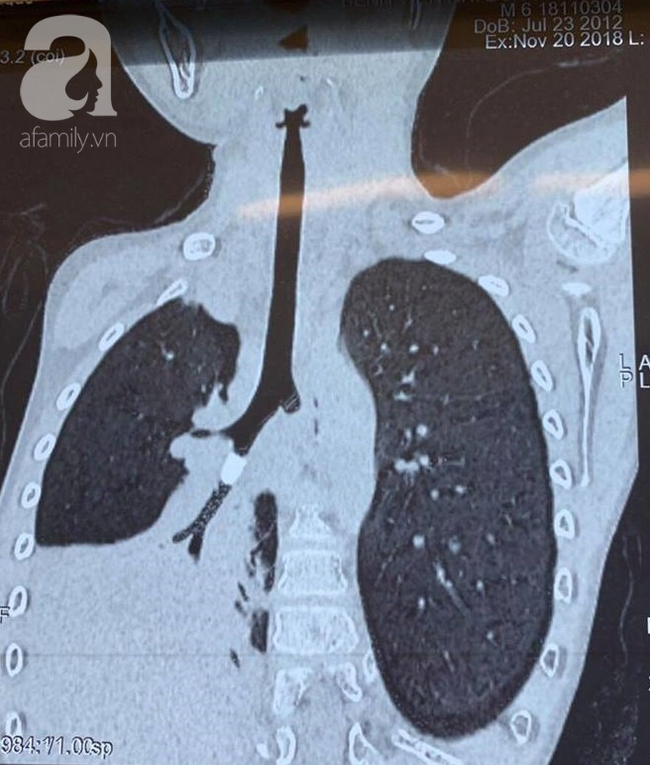

Trước đó, N. chơi ném cát với bạn cùng xóm và bất chợt có cảm giác hít sặc, ho liên tục và khó thở. Sau khi thăm khám, các BS đã nhận thấy rõ hội chứng xâm nhập và tắc nghẽn tại phổi phải. Tuy nhiên hình ảnh chụp X-quang ngực tức lại không cho thấy rõ có dị vật lạ.

TS.BS Trịnh Hồng Nhiên, Trưởng khoa Hô Hấp BV cho biết sau khi hội chẩn, ông đã chú ý đến vùng bẫy không khí trong phim chụp X-quang phổi. Kết hợp với phim CT scan ngực cho thấy có sự hiện diện của một vật thể lạ trong phế quản, dạng hình trụ, bít lòng hoàn toàn nhánh phế quản S9.

Điều này dẫn tới việc không khí không thể đi qua hoàn toàn vật thể, gây tắc và xẹp toàn bộ nửa phổi phải.

Sau khi can thiệp và lấy dị vật, Phim chụp X-quang ngực sau đó cho thấy dấu hiệu thông khí phổi tốt, tình trạng xẹp phổi phải đã được giải quyết triệt để.